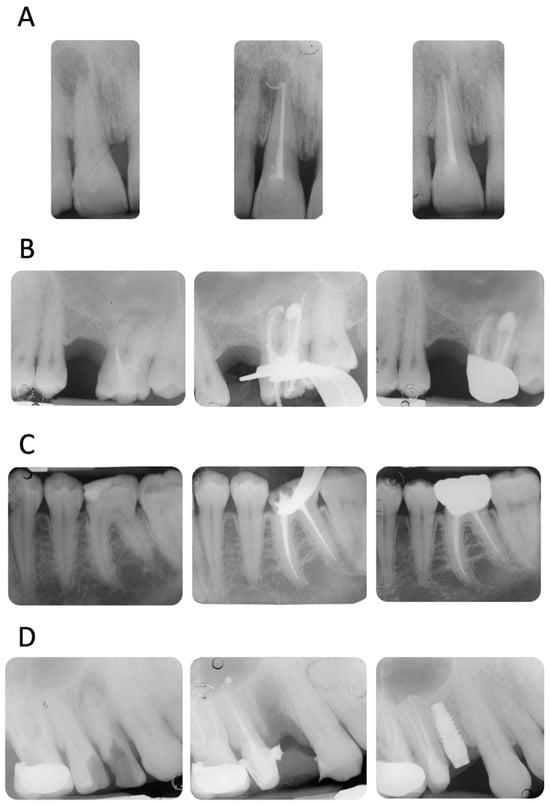

Four representative cases included in the study are reported in Figure 2A–D.

Figure 2.

(A) Upper incisor with a periapical lesion (PAI = 5). The periapical X-ray at 12 months showed resolution of the periapical pathology (PAI = 2). Note the disappearance of sealer extrusion. (B) Upper molar with previous failed root canal treatment (PAI = 4). The mesio-buccal root revealed a periapical lesion, a metal post, and an incomplete filling of the apical third. It is interesting to observe the sealer morphology after root canal obturation and after 12 months of follow-up. The extrusion around the mesio-buccal root seems to have disappeared, while the one in the palatal root is still present. No post-operative pain was reported (VAS = 0 throughout the entire treatment and follow-up). (C) Lower first molar with a deep carious lesion. Slight periapical extrusion was observed in the mesial and distal canals. Uneventful healing was observed at the 12-month follow-up. (D) Upper second premolar with a deep carious lesion and no periapical radiolucencies (PAI = 2). Slight modification of the sealer extrusion was observed at the 12-month recall.